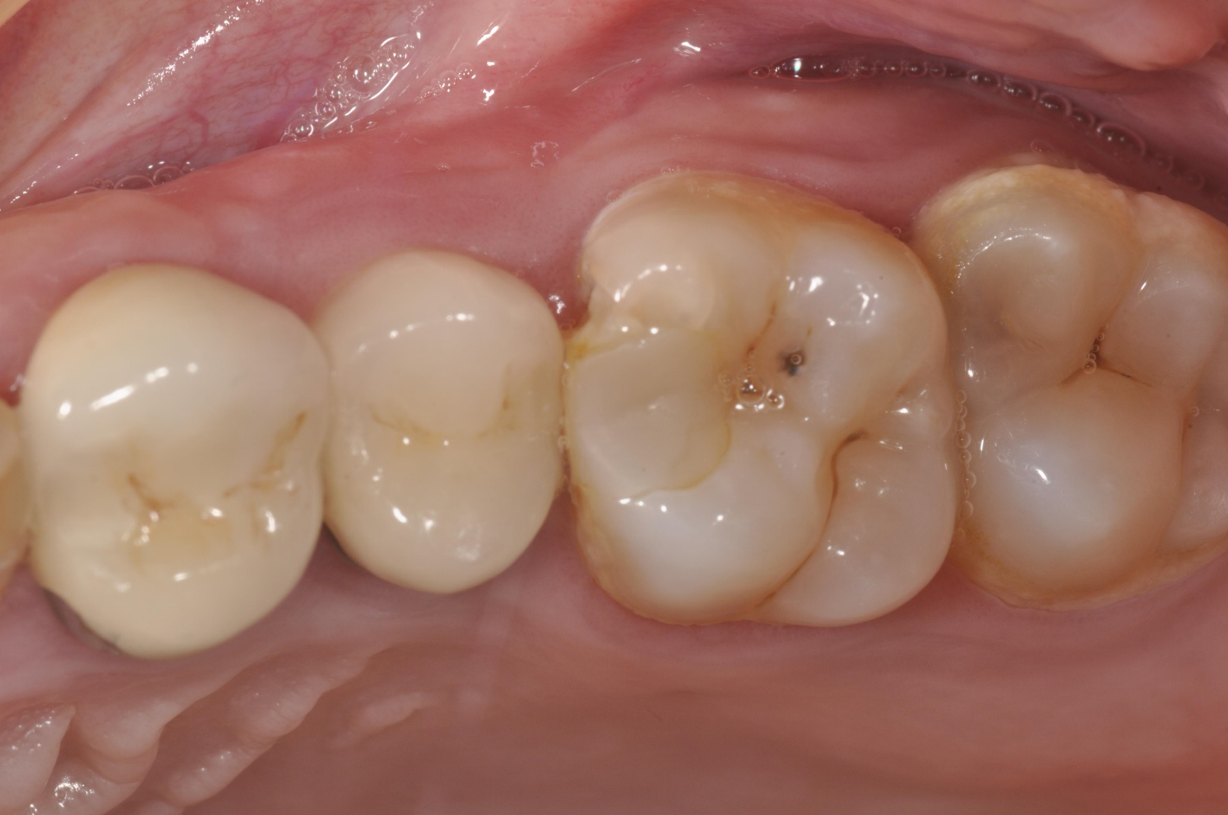

治療前,嚴重二次蛀牙

二次蛀牙